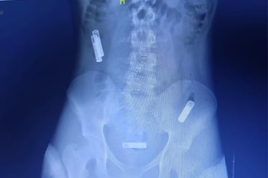

ہسپتال کے سینیئر سرجن ڈاکٹر تنمے پاریکھ کے مطابق سونوگرافی میں واضح طور پر ٹوتھ برش اور لوہے کی پانے نما اشیا نظر آئیں۔ صورتحال کی سنگینی کو دیکھتے ہوئے فوری طور پر اینڈوسکوپی کی گئی، تاہم اشیا کے حجم کی وجہ سے انہیں اینڈوسکوپی کے ذریعے نکالنا ممکن نہ ہو سکا۔ بعض نوکیلی اشیا معدے کی دیوار تک پہنچ چکی تھیں جو کسی بھی وقت جان لیوا ثابت ہو سکتی تھیں۔

بالآخر ڈاکٹروں نے اوپن سرجری کا فیصلہ کیا۔ دو گھنٹے سے زائد جاری رہنے والے آپریشن کے دوران ڈاکٹروں نے مریض کے معدے سے سات ٹوتھ برش اور دو لوہے کے پانے (رینچ) کامیابی سے نکال لیے۔